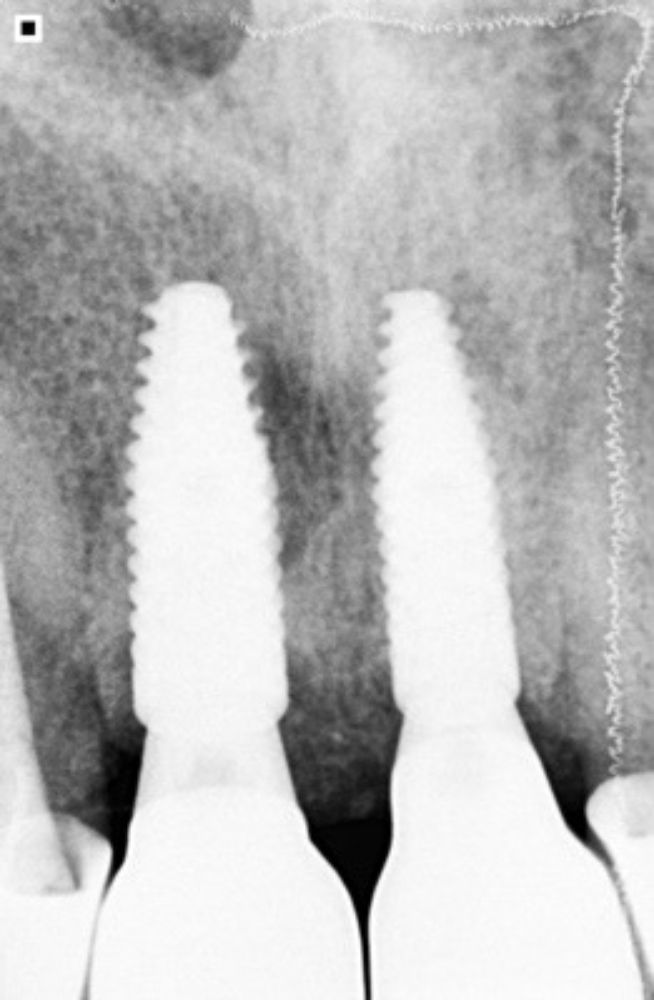

Die STL files, color assessment, and lab prescription were sent to the dental technician. The master model was 3D printed, and the crowns were fabricated. Since the substructure and an emergence profile of the crown were optimal and met the patient’s expectations, the final crowns were screwed in, and a radiographic control image was recorded. The periapical x-ray demonstrated an optimal fit (Figs. 34-39). Instructions on oral hygiene were given, and occlusion was checked.